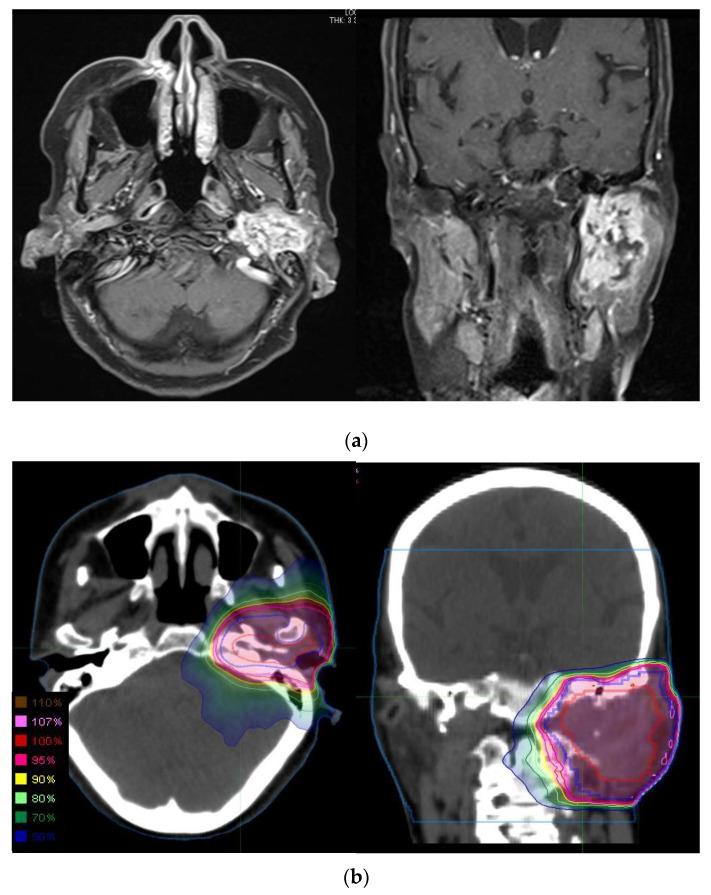

The standard treatment for adenoid cystic carcinoma of the head and neck is surgical resection followed by postoperative radiotherapy (PORT). Currently, definitive radiotherapy (defRT) is considered an inadequate treatment; however, its data are based on studies using classical radiotherapy techniques. Therefore, the therapeutic effects of current radiotherapy techniques have not been adequately evaluated, and it may have underestimated the efficacy of defRT.

We retrospectively analyzed 44 adenoid cystic carcinoma patients treated with radiotherapy based on modern treatment techniques from 1993 to 2017.

Twenty-four patients underwent PORT and 20 patients underwent defRT. The 5-year overall survival rates for patients treated with PORT and defRT were 85.3% and 79.7%, respectively. The 5-year local control rates were 82.5% and 83.1%, respectively. There were no statistically significant differences in the overall survival and local control of patients treated with PORT and defRT ( = 0.4392 and = 0.0904, respectively).

Our results show that defRT is comparable to surgical resection followed by PORT with respect to overall survival and local control. The results suggest that defRT can be an effective treatment option for adenoid cystic carcinoma of the head and neck.